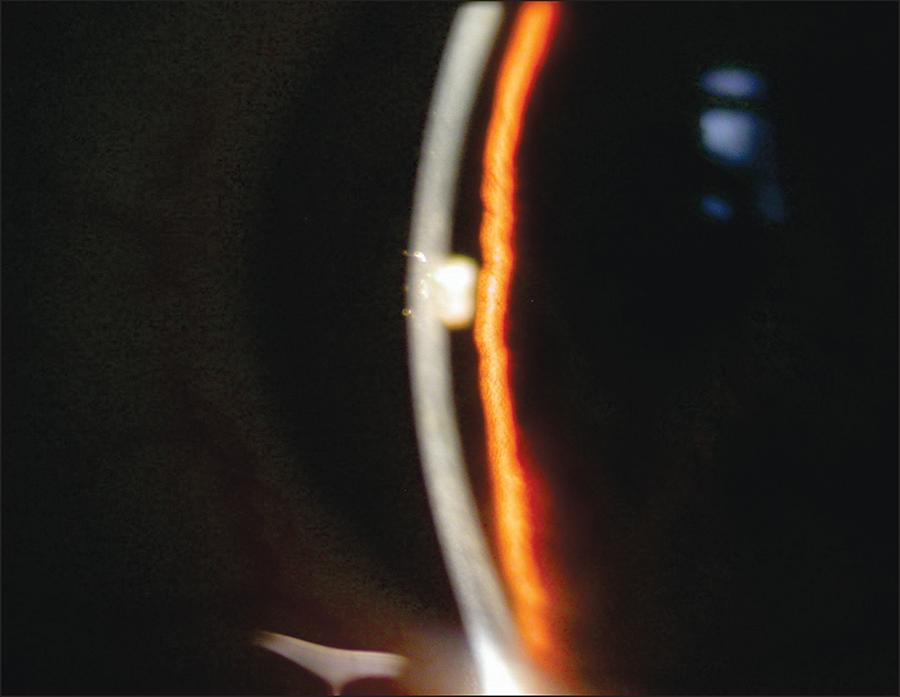

Se incluyeron siete pacientes en esta serie. Todos los pacientes tenían glaucoma avanzado que se manejó quirúrgicamente mediante trabeculectomía (6 pacientes) o válvula de Ahmed (1 paciente). Todos los pacientes presentaron presión intraocular <7 mm Ηg, cámara anterior estrecha e imágenes de desprendimiento coroideo y desprendimiento de cuerpo ciliar por ultrasonido. La hipotonía de los pacientes se trató con inyección de 0,4 a 0,6 ml de SF6 puro al 100% en cámara anterior seguida de postura en decúbito supino. El objetivo de esta inyección era doble: desplazar el cuerpo ciliar a su posición normal, restablecer la producción normal del humor acuoso, y bloquear el flujo de humor acuoso a través de la formación de burbujas, lo que provoca un aumento de la presión intraocular.

La técnica quirúrgica fue exitosa en los 7 pacientes con normalización de la presión intraocular (> 10 mm Hg) y el aumento de la profundidad de la cámara anterior en la primera semana después de la cirugía.